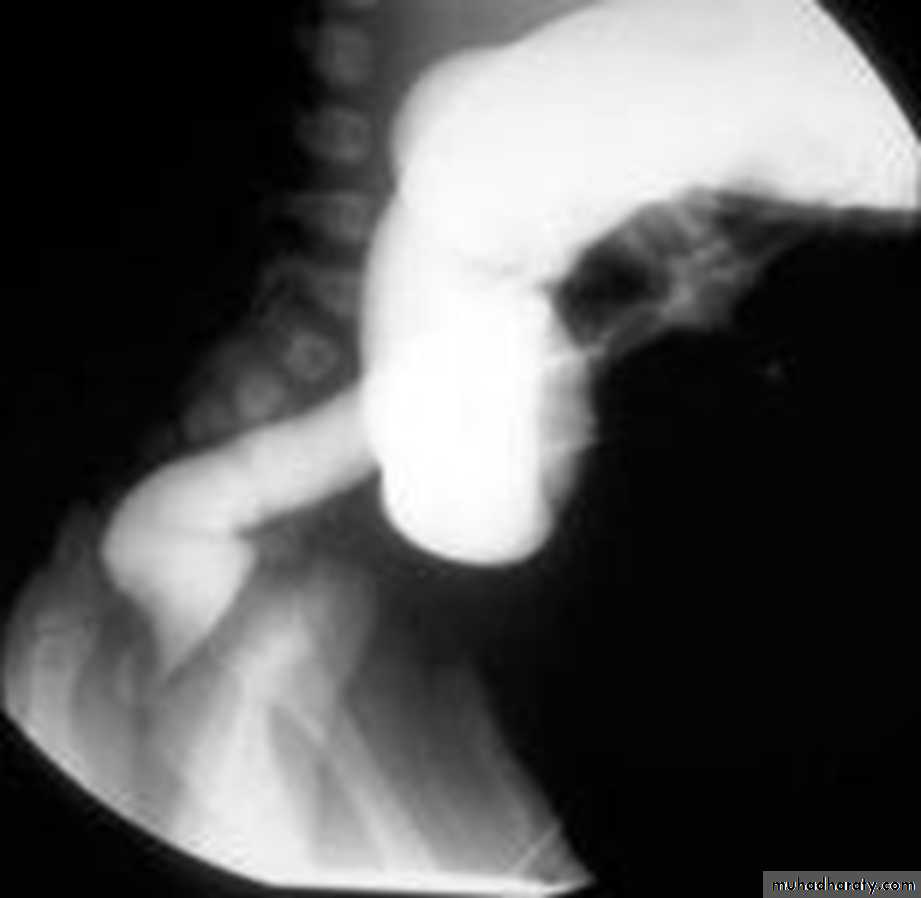

• Morphological types:• 1_ Ulcerative : give rise to irregularity of the colon with ulceration.

• 2_ Constrictive or infiltrative ( Annular ) type :

• a- Constant narrowing .

• b-Shouldering sign, apple core sign .

• c- Destruction of mucosa at narrow area .

• d- Double track due to fistula .

• e- In severe constriction ; stoppage of Ba. Flow with proximal dilatation .

apple core lesion in the descending colon